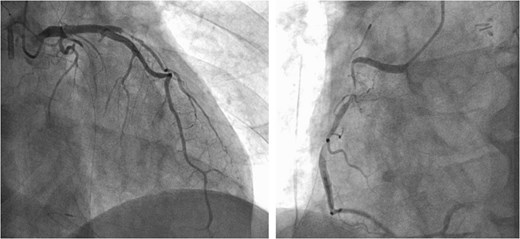

A 73-year-old male presented to his primary hospital with complaints of chest pain. Examination revealed a coronary artery-pulmonary artery fistula and 75% stenosis of the RCA (Figs 1 and 2) with a resting full-cycle ratio (RFR) of 1.0. However, myocardial scintigraphy was negative for ischemia and electrocardiogram (CAG) at rest showed no ST changes (Fig. 3). An exercise resting electrocardiogram (ECG) showed diffuse ST depression, raising suspicion of ischemia due to coronary steal (Fig. 4). Consequently, the patient was referred to our department.

Preoperative CAG showing coronary artery-pulmonary artery fistula and 75% stenosis of the right coronary artery.